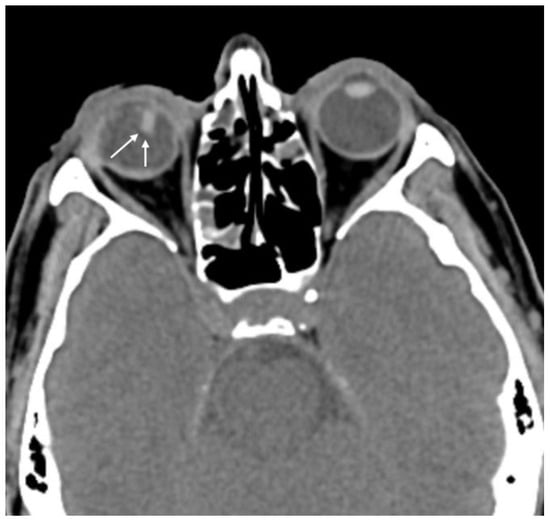

| Globe wall irregularity | 16 (53.3) |

| Asymmetric anterior chamber depth | 16 (53.3) |

| Lens dislocation | 3 (10.0) |